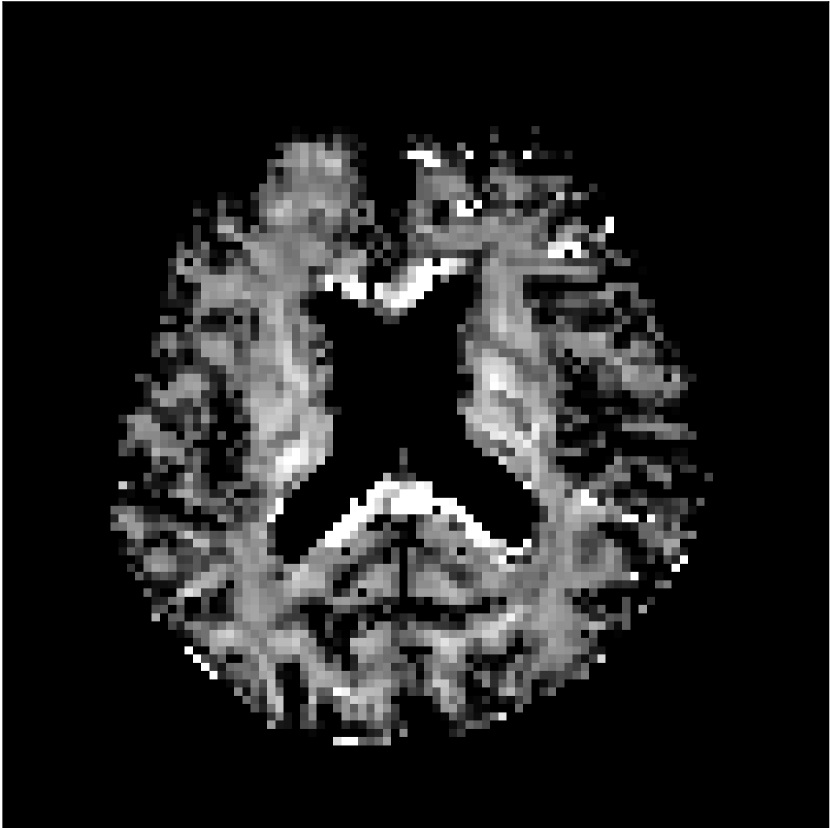

Figure 9 shows parameter maps for the different methods without partial Fourier (No PF) and with 5/8ths partial Fourier (5/8 PF). Mean diffusivities calculated from the raw DWI data (Raw) show notable noise and Gibbs ringing artifacts, while this is substantially removed with the state-of-the-art (SoA) method. However, the state-of-the-art method begins to lose its ability to compensate for the Gibbs ringing and resolution loss when partial Fourier is utilized in the acquisition. The effects of partial Fourier increases are primarily evident in the enlargement of the lateral ventricles and the presence of black lines in the vicinity of the lateral ventricles. The MCNN model is able to compensate somewhat for the ringing effects, but begins to introduce substantial artifacts at the 5/8ths partial Fourier factor, whereas the CCNN model continues to give high-quality mean parameter maps across all PF factors.

Raw

SoA

MCNN

Standard PF

CCNN

b=0𝑏0b=0 s/mm2

No PF

MD, μ𝜇\mum2/ms

5/8 PF

FA

MK

Figure 9: Parameter maps from various methods (with CSF masks for FA and MK). At the top are shown the b=0𝑏0b=0 images from Raw, state-of-the-art (SoA), MCNN, standard partial Fourier, and CCNN methods. Rows 2 and 3 show results for mean diffusivity, rows 4 and 5 show results for fractional anisotropy, and rows 6 and 7 show results for mean kurtosis. The SoA method and both deep learning methods perform well without partial Fourier acceleration; however, at the 5/8ths partial Fourier factor, substantial artifacts are present for all methods other than the CCNN method.

Similar trends are observed in the other diffusion parameter maps.